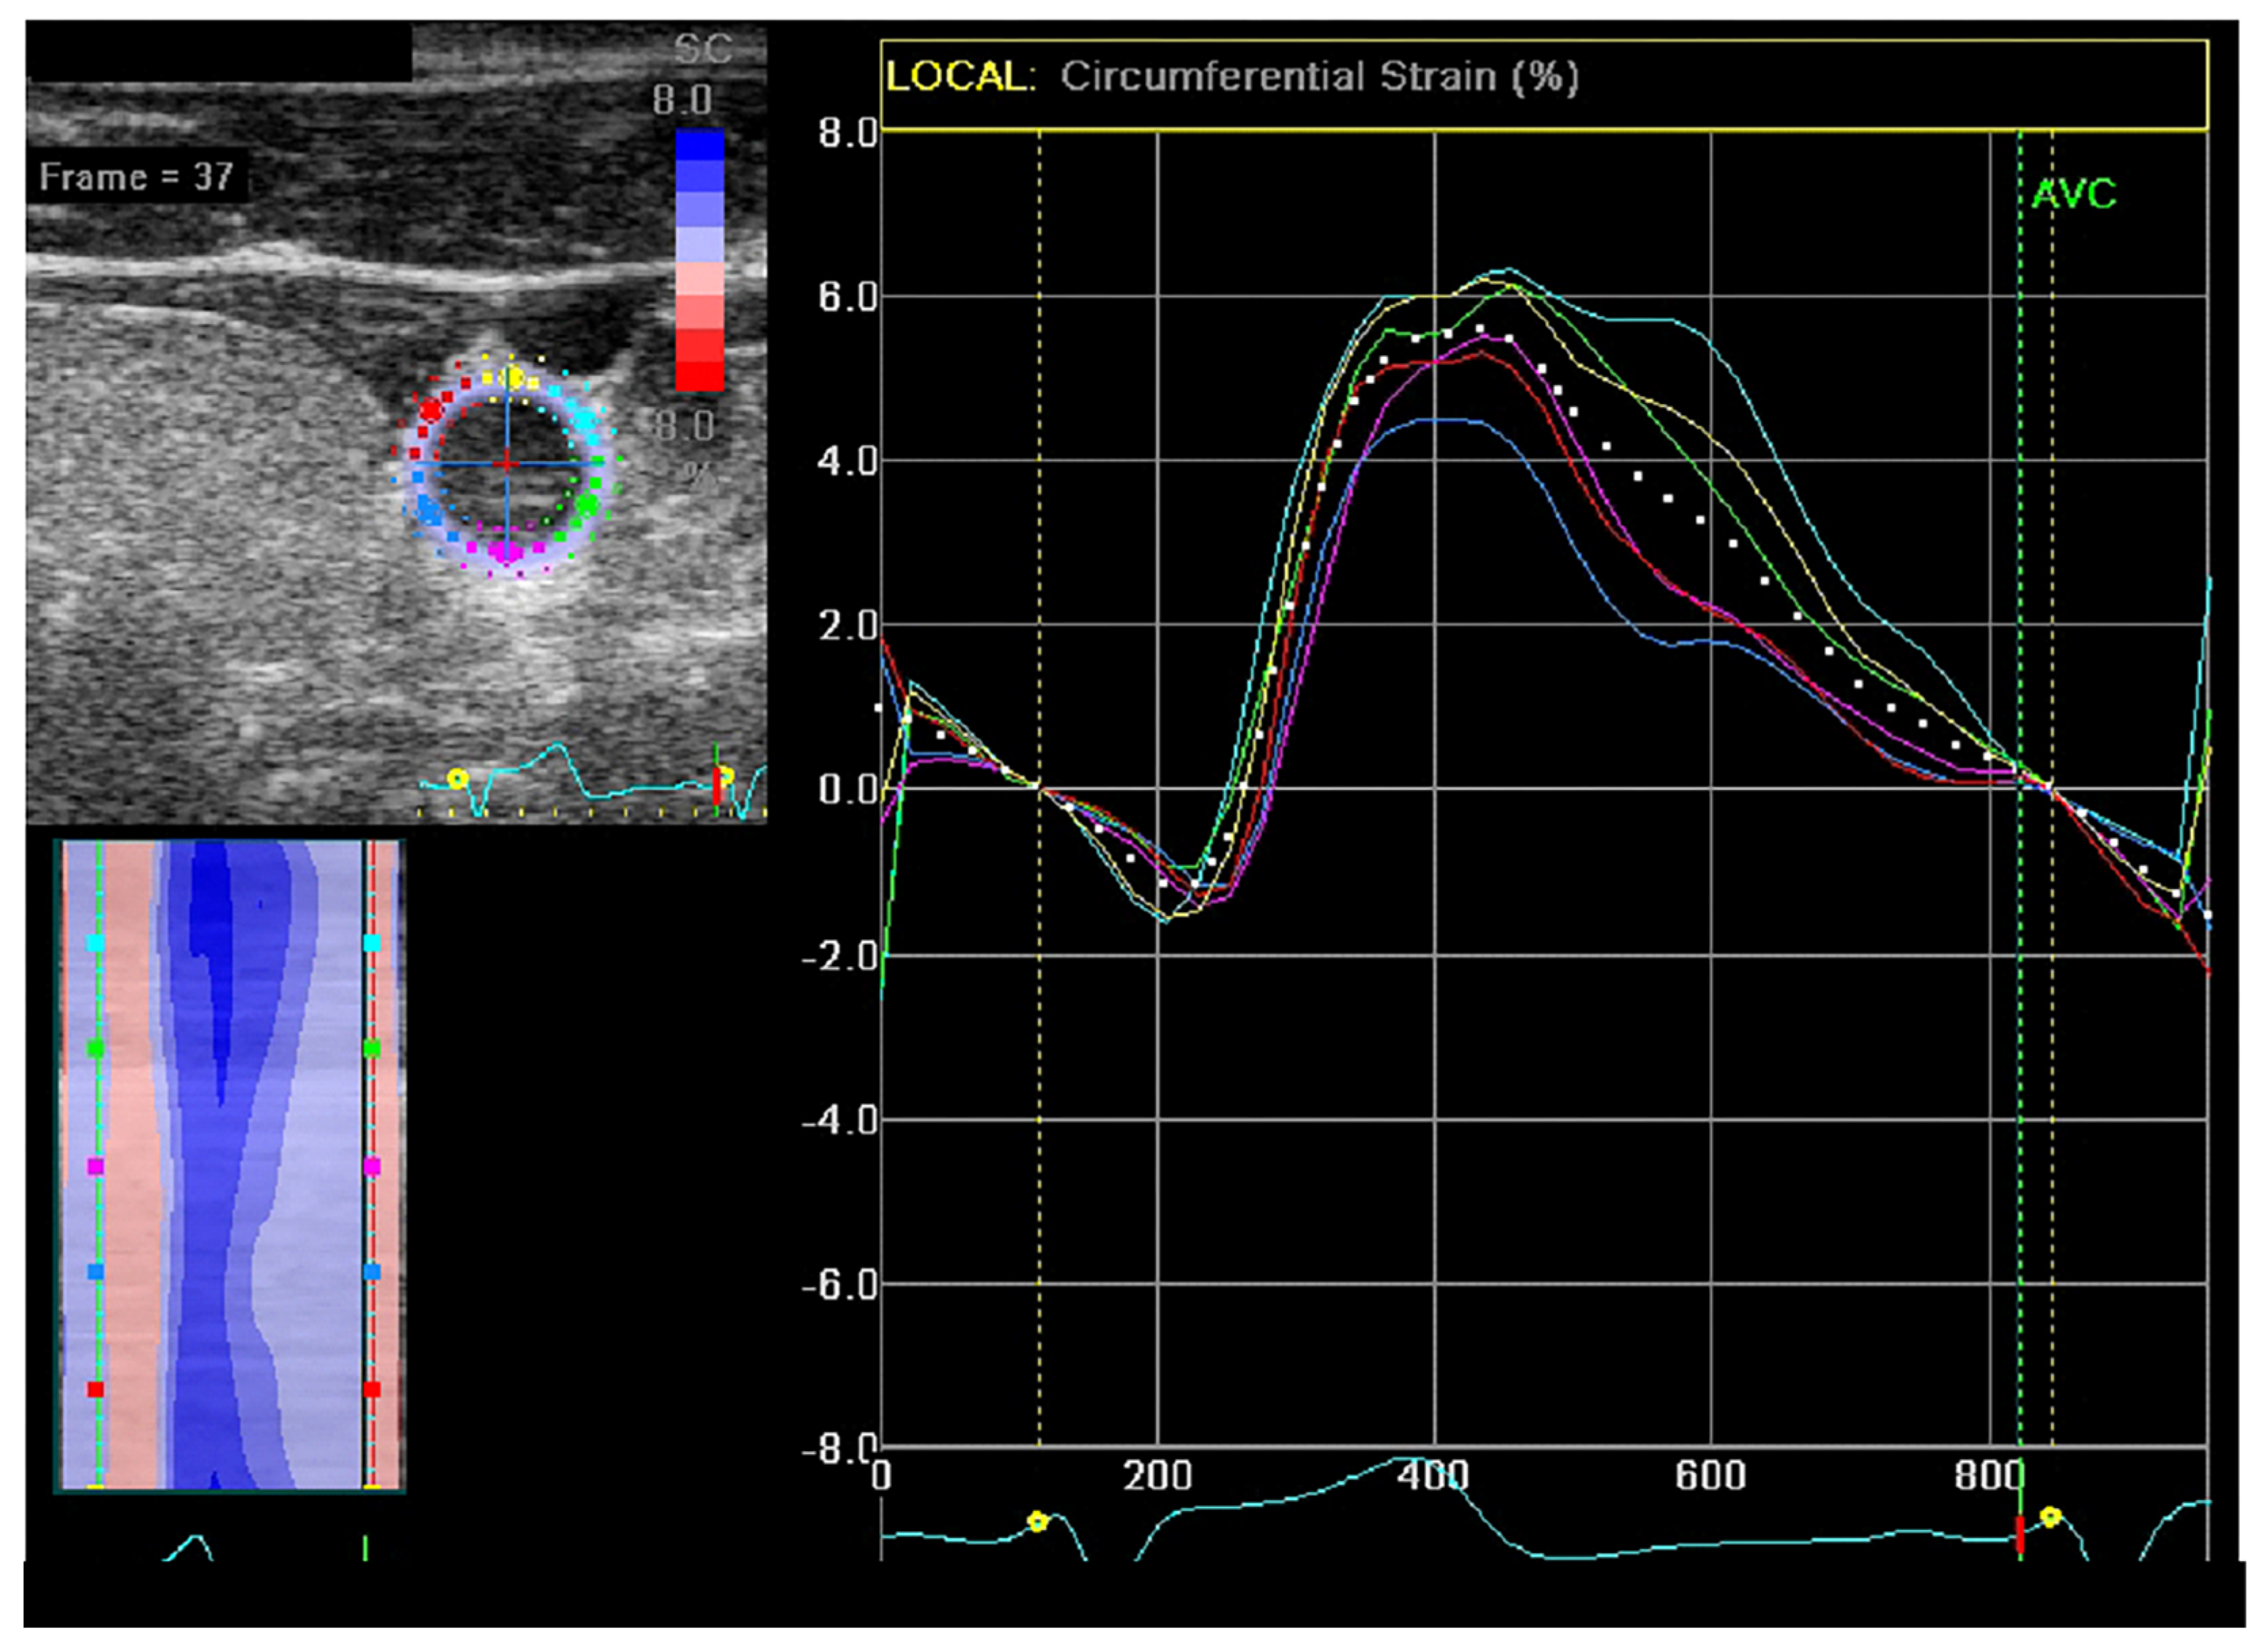

2.4. Ultrasonography CS Measurements

- Ustyniak, S.; Stefańczyk, L.; Kaczmarska, M.; Kurnatowska, I.; Goździk, M. Peripheral Arterial Response during Haemodialysis—Is Two-Dimensional Speckle-Tracking a Useful Arterial Reactivity Assessment Tool? J. Ultrason 2021, 21, 213–218. [Google Scholar] [CrossRef]